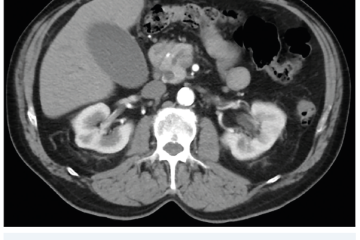

Několik studií se zabývalo AI asistovanou CT detekcí karcinomu pankreatu s AUC 0,79–0,99 %,6–8 tedy přesností porovnatelnou s přesností práce zkušeného radiologa. Stran časné detekce proběhla studie posuzující přesnost AI modelu v detekci karcinomu pankreatu v období 3–36 měsíců před prvními projevy onemocnění. Zařazeno bylo 155 pacientů s karcinomem pankreatu a 265 zdravých kontrol. AI model zde dosáhl AUC 0,98, což výrazně předčilo radiology, kteří při popisování stejných případů dosáhli AUC 0,66.9 Studie využívající DL model pro rozlišení zdravé slinivky od nálezu pankreatických neoplazií, tedy karcinomu pankreatu, intraduktální papilární mucinózní neoplazie (IPMN), serózních a mucinózních cystických neoplazií a solidní pseudopapilární neoplazie, byla prezentována s AUC 0,91, tedy opět odpovídající přesnosti popisu radiologa.10 Pro další vývoj a možné klinické využití bude potřeba přístupu k rozsáhlému archivu CT snímků karcinomu pankreatu, aby se ML modely mohly zdokonalovat. Další studie se věnovaly AI asistované diferenciální diagnostice. Ta bývá u lézí pankreatu velmi obtížná a pokrok v této problematice je tak velmi přínosný. Mezi nejzajímavější patří studie zabývající se rozlišením serózních a mucinózních cystadenomů s AUC 0,932.11 Další studie zkoumala úspěšnost rozlišení karcinomu pankreatu od zbytnění pankreatu při určitých formách chronické pankreatitidy (MFP – mass forming pancreatitis) s AUC 0,866.12 V další studii byla AI využita k rozlišení fokální autoimunitní pankreatitidy od karcinomu pankreatu s AUC 0,97.13 V rámci MR proběhlo několik studií, které se zaměřily na AI asistované zachycení a klasifikaci pankreatického karcinomu či IPMN. Studie klasifikující IPMN pomocí konvoluční neuronové sítě (CNN – convolutional neural network) byla schopna rozlišit dysplazii vysokého stupně od přítomnosti karcinomu se senzitivitou 76 %, specificitou 78 % a AUC 0,78.14 Další studie porovnávala AI modely CT a MR v predikci maligního IPMN. Výsledky ukázaly, že MR model s AUC 0,94 byl přesnější než CT model s AUC 0,864.15 S využitím PET/CT byl prozkoumán AI model rozlišující od sebe akutní pankreatitidu a karcinom pankreatu s AUC 0,9668.16 Výsledky AI v oblastech zobrazovacích metod jsou tak slibné. Dosahují minimálně přesnosti srovnatelné s radiologem a zejména v problematice časných karcinomů pankreatu člověka svojí přesností převyšují (obr. 1–5).